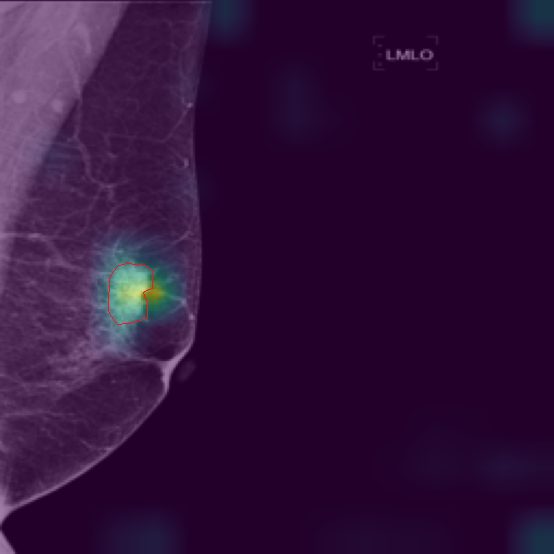

5.9 ViKL Provides Evidence for Clinical Decision

In our earlier sections, we discussed how ViKL enhances the image branch’s capability for detailed feature extraction by using text and manifestations that describe localized lumps. To directly observe this enhanced feature extraction ability, we utilize the class activation map (CAM) [62], a common tool for visualizing neural network activations. Specifically, we employ Grad-CAM [63] to generate activation maps from the third layer of the ResNet50 model, which has been fine-tuned using ViKL on the MKVL dataset. Additionally, for accurate visualization and comparison, we include markings of lumps as annotated by professional radiologists. The results of this visualization are showcased in Fig. 6. These visualizations demonstrate ViKL’s effective localization of small lesions, highlighting its refined ability to capture minute features in medical imaging.